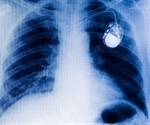

Implanted devices are giving cardiologists a new view of subtle changes in a key measurement of heart health

Study aims to help heart patients adapt to implanted defibrillators

Implantable defibrillator cuts heart attack risk of sudden death by 31%